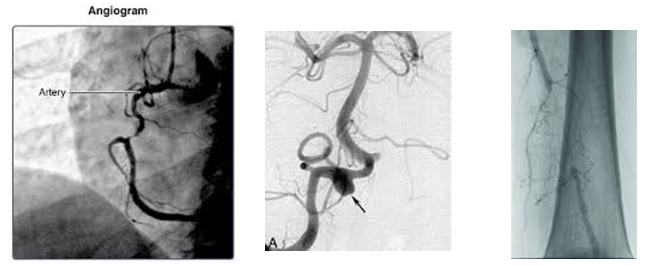

Podríamos decir entonces que las arteriografías y las flebografías son radiografías de arterias o venas de una determinada región u órgano del cuerpo.

Imagen 1

Debido que estas estructuras son normalmente invisibles a los Rayos X, para poder estudiarlas es preciso llenarlas por dentro de un material de contraste a base de yodo. Con el mismo, se crea un molde de líquido que delinea perfectamente el interior de estos vasos pudiendo ser capturada entonces la imagen mediante un aparato de Rayos X. Sería algo así como sacar radiografía a un vaso de plástico vacío y a otro colmado de material de contraste. El primero sería invisible mientras que en el caso del segundo, veríamos la forma que adopta el líquido dentro del recipiente.